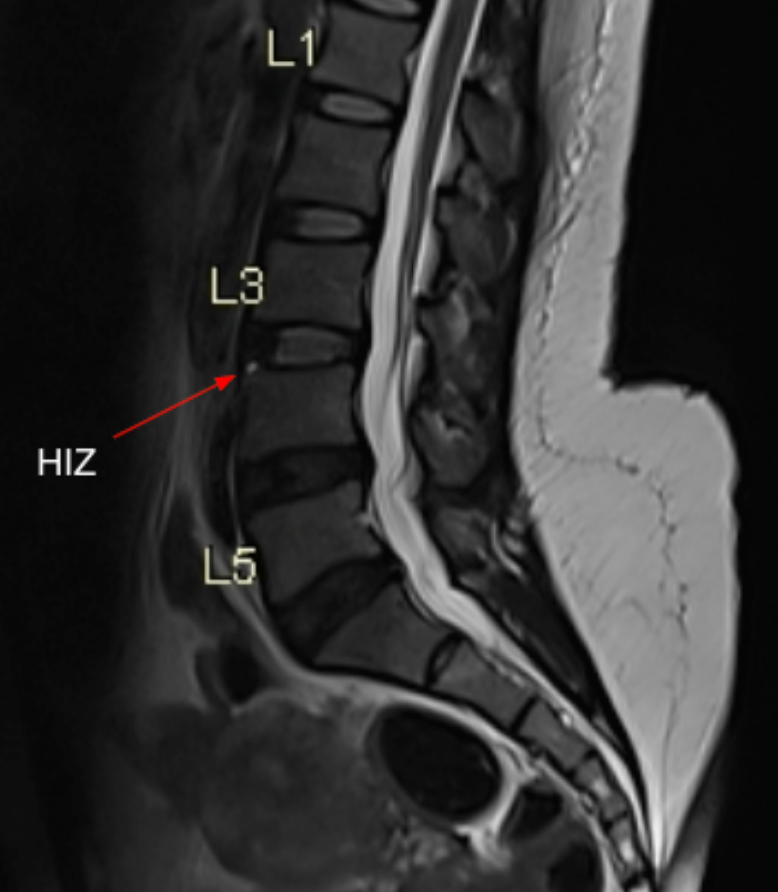

The High-Intensity Zone (HIZ) is defined as a focal area of increased signal intensity within the posterior annulus fibrosus on T2-weighted MRI that is clearly distinct from the nucleus pulposus. It represents an annular fissure/tear and is strongly associated with discogenic low-back pain, particularly when concordant with patient symptoms.

• Scroll through the mid-sagittal and parasagittal T2 sequences of the lumbar spine.

• Identify a well-defined hyperintense focus located within the posterior annulus fibrosus, separate from the nucleus pulposus.

• Disc level (e.g., L4–5)

• Location (central, right or left posterolateral)

• Focal T2 hyperintensity in posterior annulus: Annular fissure / HIZ